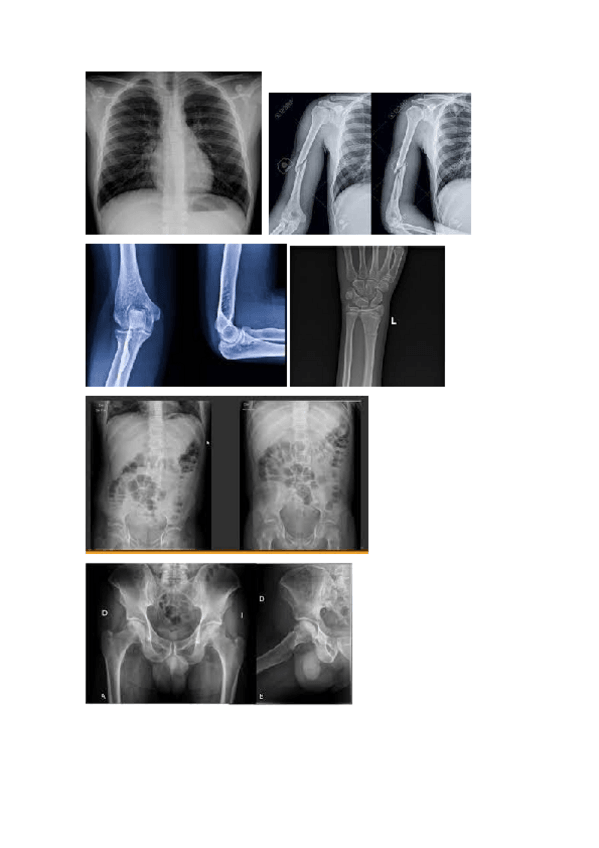

1º Imagen para el diagnóstico y medicina nuclear Apuntes anatomía. HOMBRO, CODO Y MUÑECA

1º Imagen para el diagnóstico y medicina nuclear Apuntes de anatomía. LA CADERA Y EL FÉMUR

He publicado nuevos apuntes de Anatomía por la imagen: Imagenes-radiograficas-con-solucion-ARTICULACIONES.pdf

43 páginas